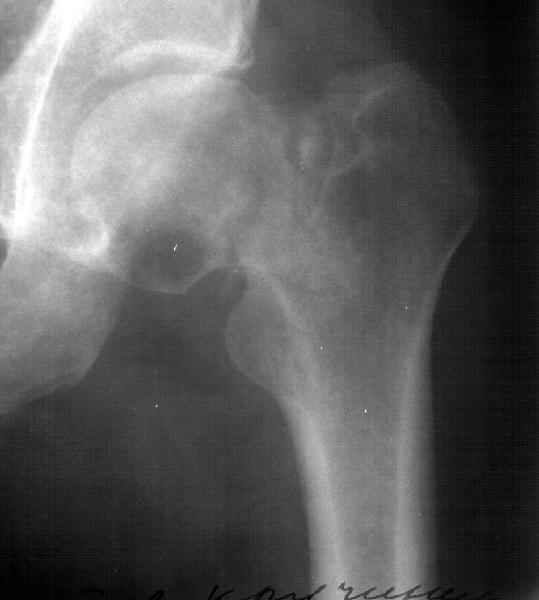

А что насчет остеостомии типа как на картинке в приложении?

Вчера сделали остеотомию, делали близко к тому, как на той картинке.

Картинка тут.

То, что получилось, в приложении (без такой красивой анимации, к сожалению